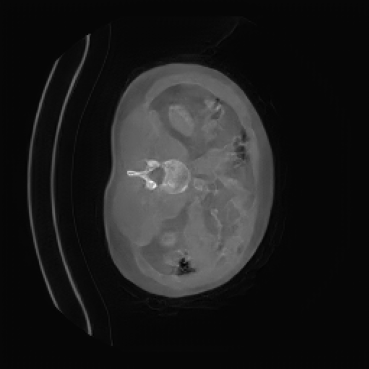

The motivation for this work arises from the need to address these limitations in the synthesis of 3D medical images. Current techniques do not produce high-resolution 3D images that preserve spatial coherence and capture the full complexity of medical data, as shown in Figure 2, 5. The development of advanced 3D generative models tailored specifically for medical imaging could not only improve the quality of synthetic medical images but also help alleviate data scarcity, enhance privacy protection, reduce computational requirement and ultimately advance the use of deep learning in healthcare applications.

To demonstrate the advantages of 3D semantic image synthesis over 2D semantic semantic image synthesis, we conducted a detailed comparison with the SegGuidedDiff [26] model. SegGuidedDiff generates medical images based on 2D semantic maps, producing individual 2D slices that are later stacked to form a 3D image. However, this approach has limitations in capturing spatial continuity and coherence across slices, which is critical for representing the spatial structure of 3D medical images. As a result, inconsistencies often arise between different slices, particularly in preserving anatomical structures across the coronal and sagittal planes. The generated images exhibit varying levels of denoising, resulting in differences in brightness and sharpness across the images. This inconsistency in denoising can lead to noticeable variations in visual quality, where some regions appear clearer and others less distinct.

As shown in Figure 5, the generated slices exhibit high consistency across adjacent slices. The anatomical structures and semantic patterns are smoothly and coherently preserved between slices, indicating that our model is capable of generating 3D-consistent synthetic images rather than isolated 2D slices.

In our approach, we employ a compression factor of 4 to encode 3D medical images into the latent space. This level of compression reduces the spatial resolution of the original image (e.g., from 256×256 to 64×64 per slice), while still preserving the essential anatomical structures and semantic content. The latent representation at this scale offers a favorable trade-off between dimensionality reduction and semantic fidelity. Specifically, although fine-grained textures are simplified, key structural patterns (e.g., organ boundaries, lesion shapes) remain visually distinguishable and semantically coherent. As the compression rate increases, the latent representations become progressively more abstract. With lower compression (e.g., 2× or 4×), the latent features preserve key anatomical structures and spatial layouts, making them beneficial for our semantic image synthesis task in latent space, as the model can operate on compressed representations that retain sufficient semantic information without being overwhelmed by high-frequency noise. In contrast, higher compression rates (e.g., 8× or above) lead to a loss of fine-grained details and reduced semantic fidelity. The choice of a 4× compression thus ensures that the latent features are compact and meaningful, facilitating effective conditional generation while significantly reducing computational overhead. We therefore adopt a 4× compression as a compromise between computational efficiency and semantic preservation. The corresponding 2D slices in image space and latent space are shown in Figure 7.

Figure 8 further supports these findings: the images generated by Med-LSDM preserve spatial coherence across coronal and sagittal planes, whereas those from SegGuidedDiff show noticeable inconsistencies. These artifacts likely result from the 2D nature of SegGuidedDiff, which fails to account for 3D spatial relationships. In contrast, our model’s volumetric diffusion framework inherently preserves anatomical consistency, highlighting its advanta in synthesizing high-fidelity 3D medical images.